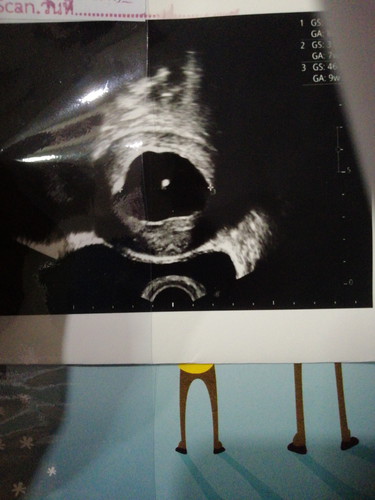

สวัสดีคะแม่ๆ คือเรามีเรื่องมาเล่าไห้ฟังคะวันนี้เราไปหาหมอด้วยเรื่องเลือดออกครั้งที่แล้วที่เคยโพสต์ไปแล้วหมอได้ทำการตรวจทั้งภายในตรวจทั้งปากมดลูกว่าเปิดไหมซาวดูแล้วหมอก็บอกว่าปากมดลูกยังไม่เปิดและยังไม่เจอตัวเด็กแต่มีจุดสีขาวๆหมอเลยบอกว่าคุณแม่ท้องกี่สัปดาห์เราก็บอกไปว่า12 สัปดาห์แต่มีพีคกว่านั้นแฟนเราถามหมอว่าอายุครรภ์ที่ตรวจหมอคิดว่ากี่สัปดาห์หมอบอกว่า8สัปดาห์เท่ากับ2เดือนตอนแรกเราก็จะเอาออกแต่หมอถามเราก่อนตรวจทุกอย่างว่าอยากมีลูกไหมเราบอกอยากมีหมอเลยบอกว่างั้นไห้รอกลับมาใหม่ถ้าไม่มีการพัฒนาก็ต้องทำใจออก และ ก็อีกกรณีหมอบอกว่าถ้าเราเป็นท้องลมถุงมนท้องจะหลุดออกมาเองแต่นี่เรามีแค่เลือดออกคล้ายประจำเดือน เรามีรูปมาไห้แม่ๆดูด้วยคะ อันนี้เป็นรูปการตรวจภายในกับการซาวหน้าท้อง(เราต้องเชื่อหมอใช่ไหมคะเพราะหมอบอกว่าจะดูว่าการตั้งครรภ์เป็นตั้งแต่แรกหมอขอยึดเครื่องซาวเป็นหลักเพราะขนาดถุงมันเท่ากับคนท้อง2เดือน)